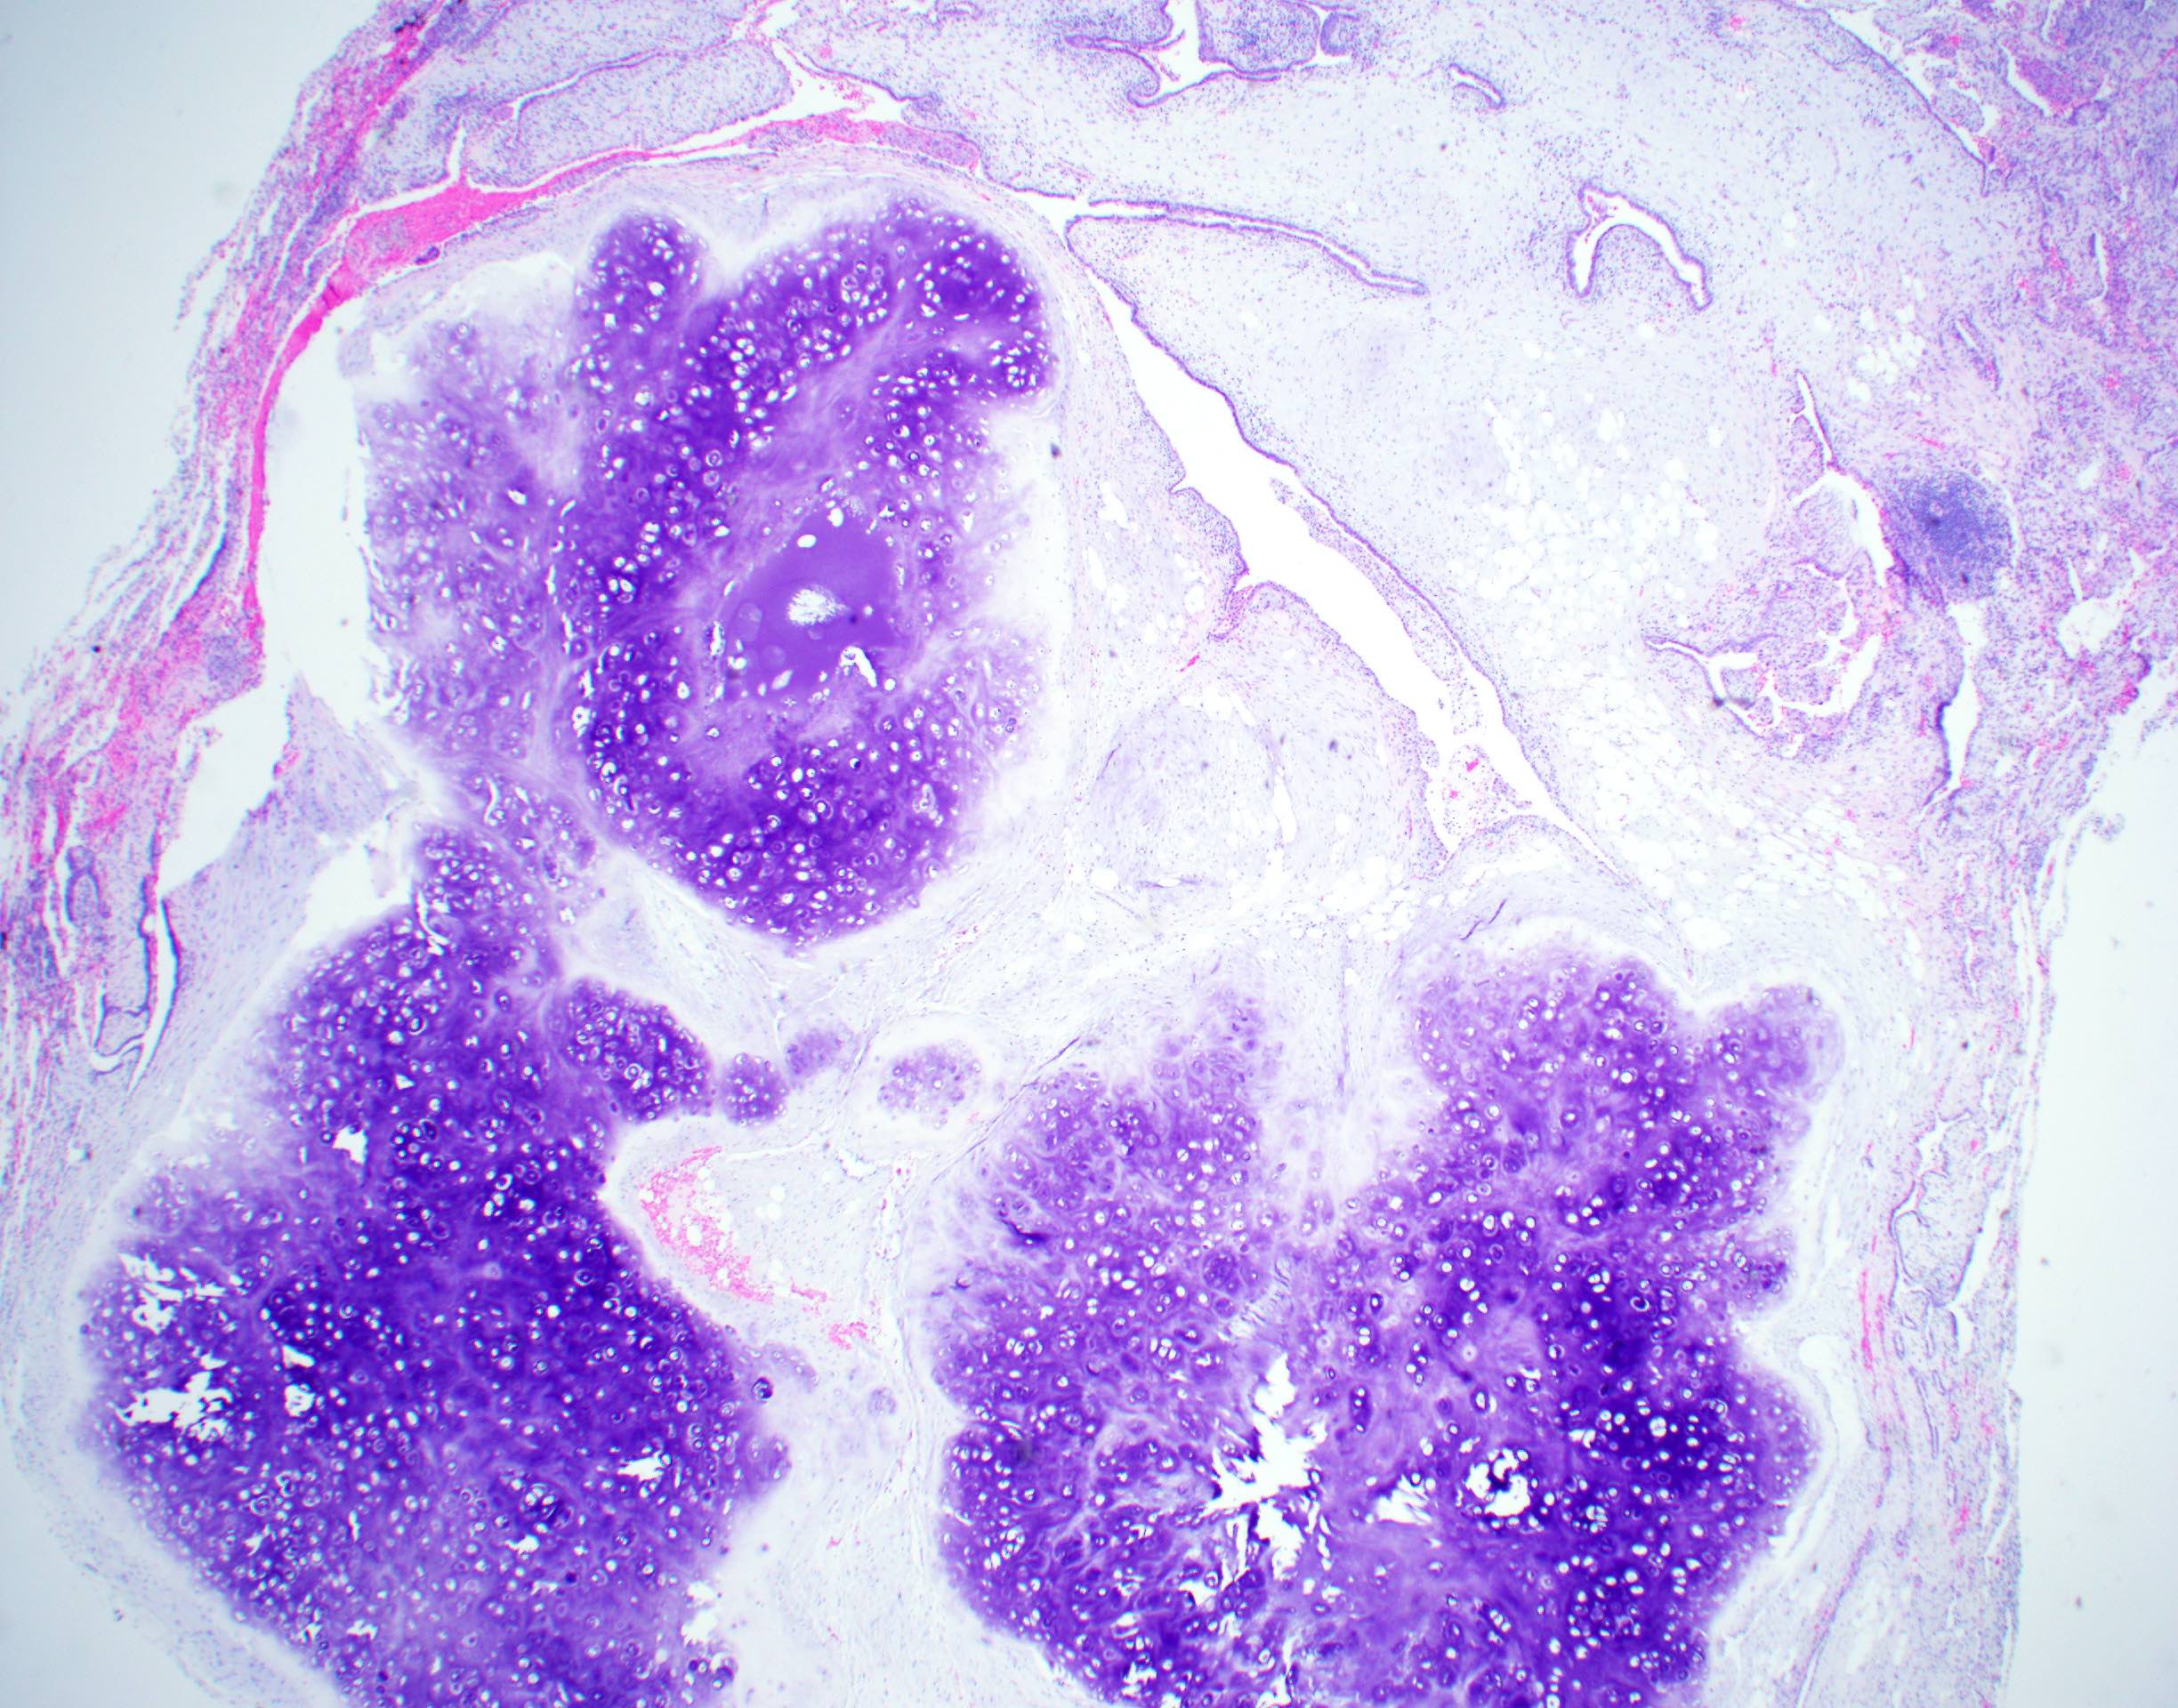

Microscopic (histologic) description

- Composed predominantly of varying degrees of mesenchymal tissue: hyaline cartilage, fat, smooth muscle and bone

- Other connective tissue elements may be present, represented by bland spindle cells, fibrous tissue or myxoid change

- Variably conspicuous, entrapped benign epithelial cells

- Reference: Thorax 1987;42:790

Microscopic (histologic) images

Contributed by Hui-Hua Li, M.D., Ph.D. and Jefree J. Schulte, M.D.

Contributed by @Andrew_Fltv on Twitter